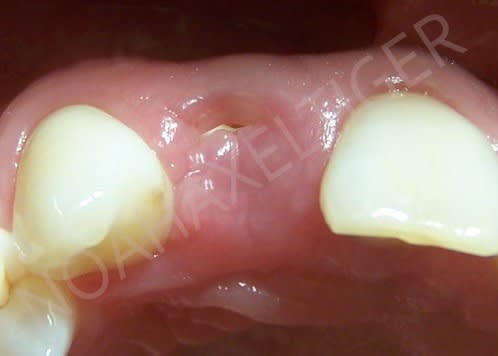

Tout à fait jeamba. Comme tu le dit très justement il n'est pas facile de pouvoir recouvrir la membrane recouvrant ton comblement à moins de :

1- faire un lambeau tracté coronairement (ce qui bride le vestibule et est préjudiciable au niveau antérieur)

2- ou bien faire un conjonctif enfoui (ou pédiculé palatin pour le maxillaire).

Une autre alternative est comme tu le dis d'extraire, d'attendre une cicatrisation des tissus mous (2 à 4 semaines) avant de passer au comblement.

J'ai également trouvé une autre alternative dont je n'ai vu personne d'autre utiliser. Comme vous êtes sympas je vous fait part de ce petit truc utile: prenons l'exemple présenté sur le photos ci jointe où une 22 fracturée doit être extraite. Le principe que j'ai mis au point est de meuler la 22 de facon à enfouir la racine à un niveau sous gingival, quaisiment juxta osseux et d'attendre quelques semaines avant de passer à l'extraction. Cela à pour conséquence un recouvrement radiculaire par les tissus gingivaux. Une fois la racine enfouie, je n'ai plus qu'à ouvrir, extraire au periotome, faire mon comblement si besoin, placer ma membrane et suturer mon lambeau sans avoir à le tracter, ou presque.

> Et que fais-tu comme tempo dans le cas montré ?

J'ai conservé la couronne de la 22 que j'avais séparé de la racine et je l'ai collé aux dents adjacentes. Facile et rapide, il faut juste penser à ne pas comprimer la gencive avec le provisoire.